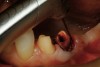

Figure 13  Preoperative view of a fixed partial denture that spanned anteriorly from tooth No. 18 to tooth No. 21. There was a minor biologic width encroachment on the distal aspect of the anterior abutment, tooth No. 21. The anterior abutment also had recurrent facial decay apical to the restorative margin and a lack of attached gingiva on the facial aspect.

Figure 13

Figure 15  After removal of the defective restoration, it can be seen clinically that the margin of the preparation on the distal of tooth No. 21 was extremely subgingival. The surrounding periodontium was inflamed and hemorrhagic. The laser was used to perform apical repositioning of the bony crest using a closed-flap technique.

Figure 15